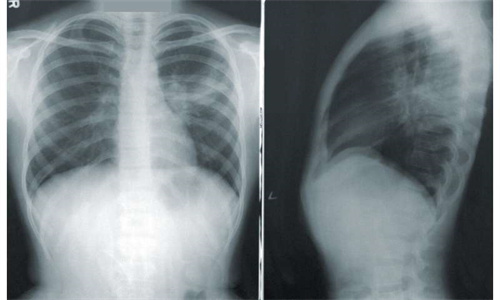

在他们的新社论中,来自内布拉斯加大学医学中心的研究人员巴维娜·夏尔马和卓义峰·基肖尔·甘蒂讨论了为老年人提供更好的肺癌护理的挑战和机遇。肺癌是美国第三大常见癌症,仅次于女性乳腺癌和前列腺癌。与任何其他类型的癌症相比,它在男性和女性中导致了更多的癌症相关死亡。

1999年至2019年期间,新肺癌的发病率有所下降,反映了过去几十年烟草使用的下降。随着筛查技术和治疗策略的更新进展,肺癌相关死亡率也有所下降。然而,肺癌的发病率和肺癌死亡率在老年患者(65岁及以上)中仍然不成比例地高。